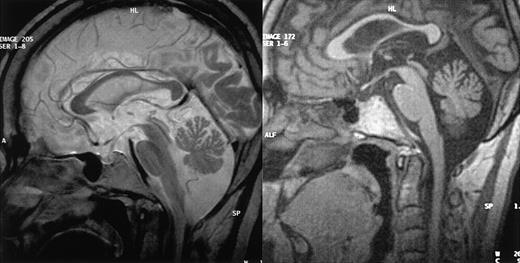

MRI results. MRI of CNS from patients 1 (left) and 3 (right), in sagittal view, showing cerebellar volume loss in both cases but normal brainstem size.

Patient 1. This patient was designated patient 1 in our initial report.9 The diagnosis of CHS was made when he was 2.5 years old and confirmed by the detection of a CHS1/LYST mutation (C3310T leading to R1103X, described in Certain et al5 as patient 2). The patient underwent allogeneic BMT at the age of 5 years. The initial outcome was largely uneventful with mixed chimerism (> 90% of donor-derived cells) that was stable over time.9 The patient is now 28 years old and has had no recurrent infections or hemophagocytic syndrome episodes in the last 23 years. He was unable to follow normal schooling and now works in a protected environment. At the age of 20 years, he developed type 2 diabetes. After the age of 22 years, he complained of increasing difficulty walking and climbing stairs and a loss of balance. Neurologic evaluation when he was 27 years old demonstrated moderate cerebellar ataxia, proximal weakness in all 4 limbs, and absent deep tendon reflexes, but no motor or sensory deficit. Electrophysiologic studies showed moderate distal motor-sensory axonal neuropathy. Cerebral MRI findings consisted of supratentorial and cerebellar volume loss (Figure 1A). A peripheral nerve biopsy specimen is shown in Figure 2B,D.

Patient 3. This patient was not included in our initial report. The diagnosis of CHS was made when she was 5 years old. She had incomplete bilateral blindness due to oculocutaneous albinism. One phase of hemophagocytic syndrome was treated with VP-16 and cyclophosphamide and the patient underwent HLA-identical BMT, with her brother as the donor, at the age of 7 years (conditioning regimen: 16 mg/kg busulfan, 200 mg/kg cyclophosphamide, and antithymocyte globulins). Her subsequent clinical condition was satisfactory. No manifestation of hemophagocytic syndrome occurred after transplantation and sustained mixed chimerism (95% of donor-derived cells) was demonstrated. The patient displayed moderate mental retardation and was able to work in a protected environment. At the age of 24 years, she began to suffer from gait abnormality and falls when walking, myoclonus, and tremor. Symptoms progressed over the next 2.5 years, and the patient is now unable to walk or to deal with daily life without constant help. Neurologic evaluation, when she was 28 years old, demonstrated nystagmus, massive cerebellar ataxia, and absent deep tendon reflexes but no motor or superficial sensory deficit. Electrophysiologic studies showed axon loss in the sural nerve. MRI and neuromuscular biopsy results are shown in Figures 1B and 2A,C.